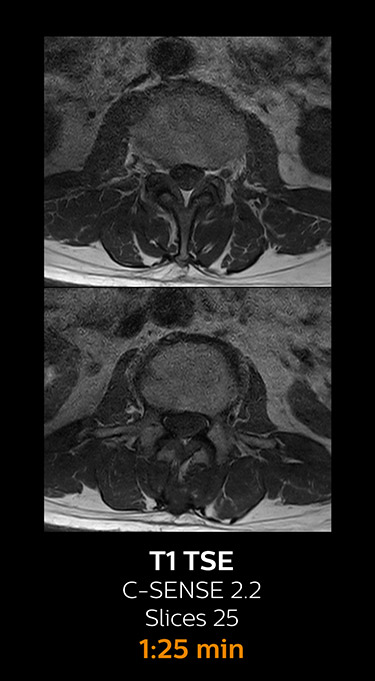

MRI examination of the lumbar spine with Compressed SENSE

Ingenia 3.0T CX

Scan time 8:17 min. (was 11:41 min. without Compressed SENSE)

With Compressed SENSE, the scan time for the routine lumbar spine examination at KNC was reduced from 11:41 to 8:17 minutes,

which corresponds to 34% reduction.